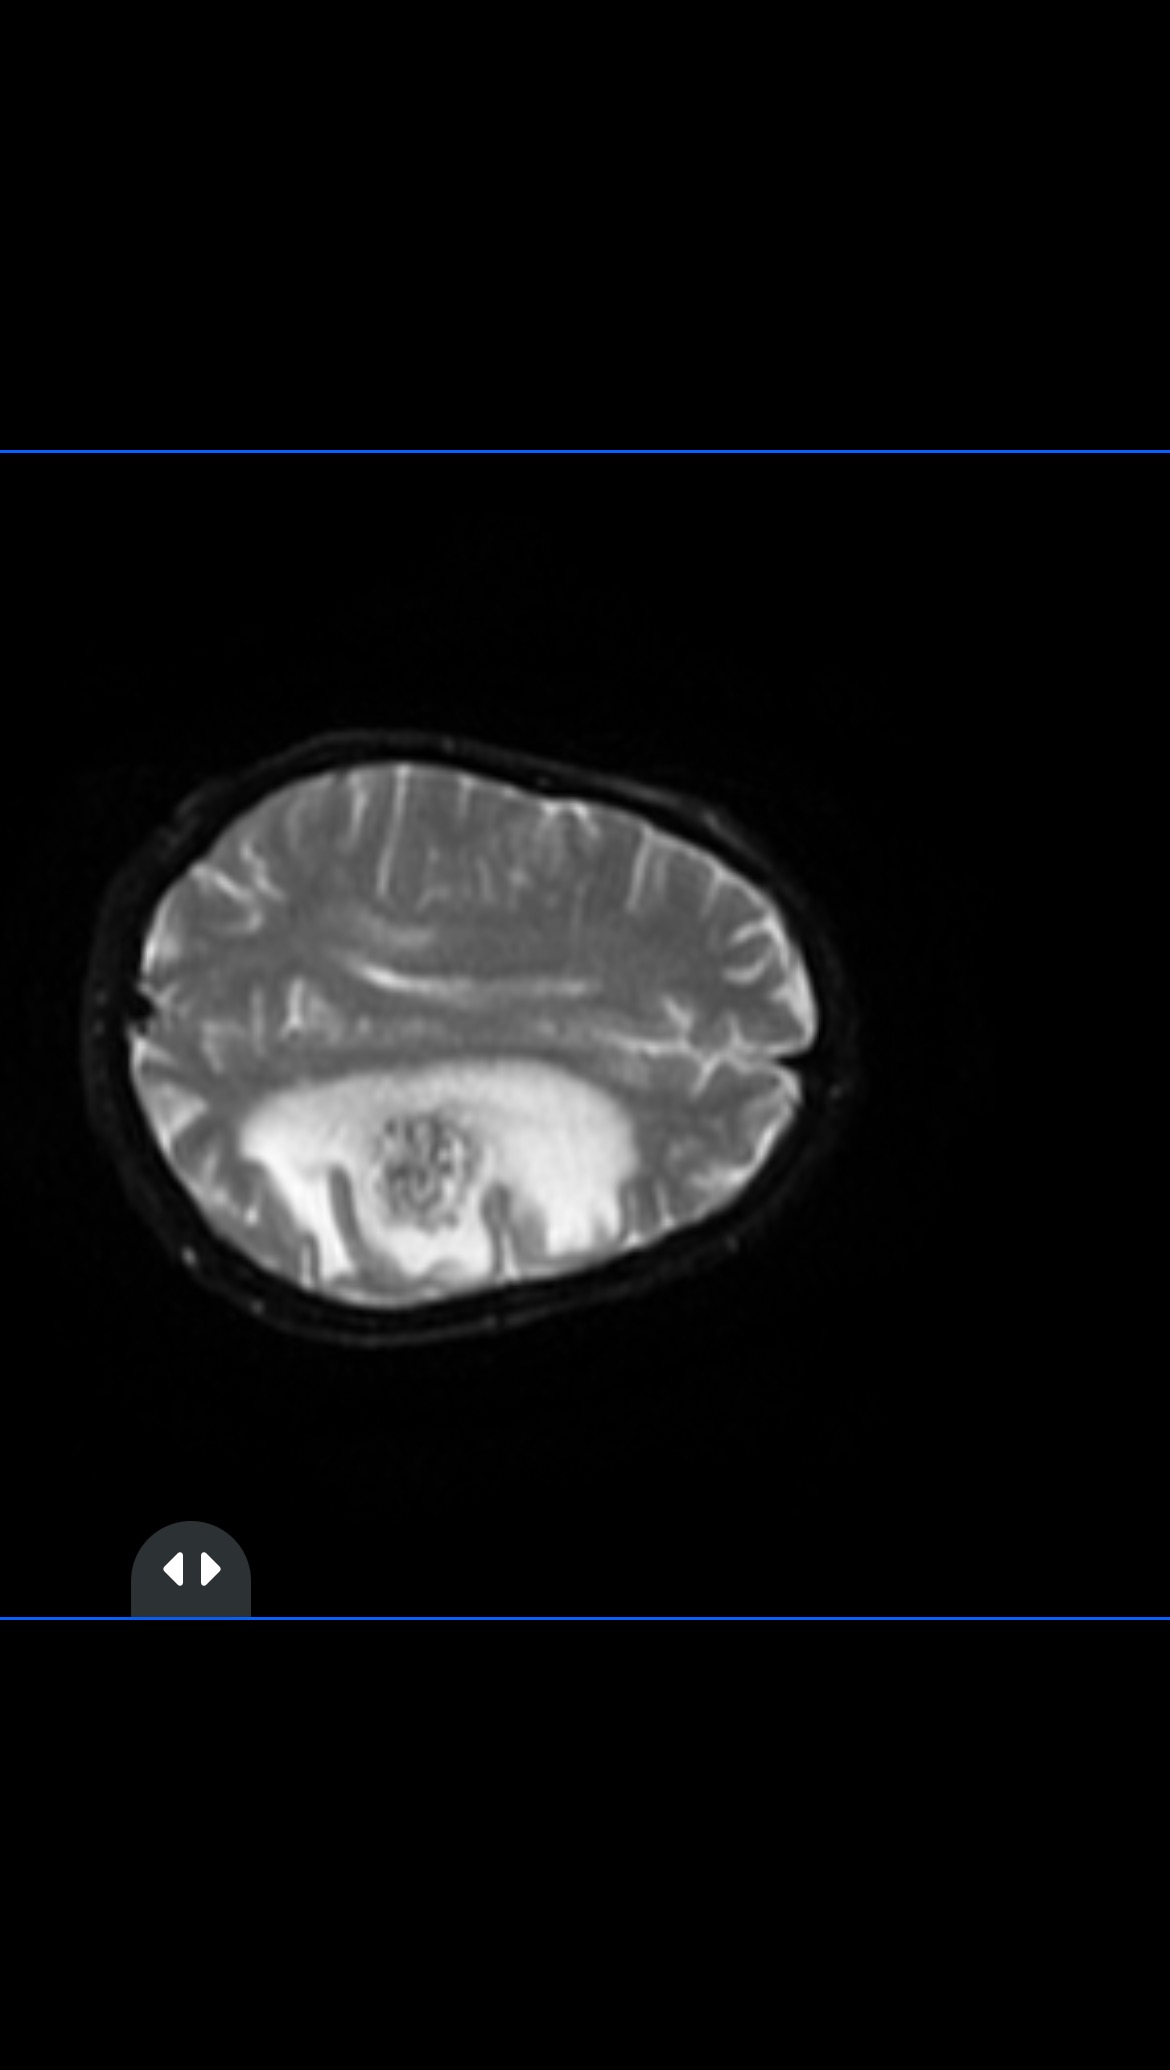

This year has been especially difficult for our family. My mom was recently diagnosed with brain metastasis from small cell lung carcinoma. She has been fighting this cancer since 2003, when I was only 7 years old. After many setbacks and recoveries, her last major battle was in 2011. For many years, she kept going—strong, active, and very much herself—until just two weeks ago.

That’s when she suddenly lost her ability to move, speak clearly, and eat on her own. From that moment on, her life—and ours—changed completely. She can no longer move the right side of her body, has cognitive impairment, struggles to communicate, and is now fully dependent on others for eating, using the bathroom, and all basic daily activities.